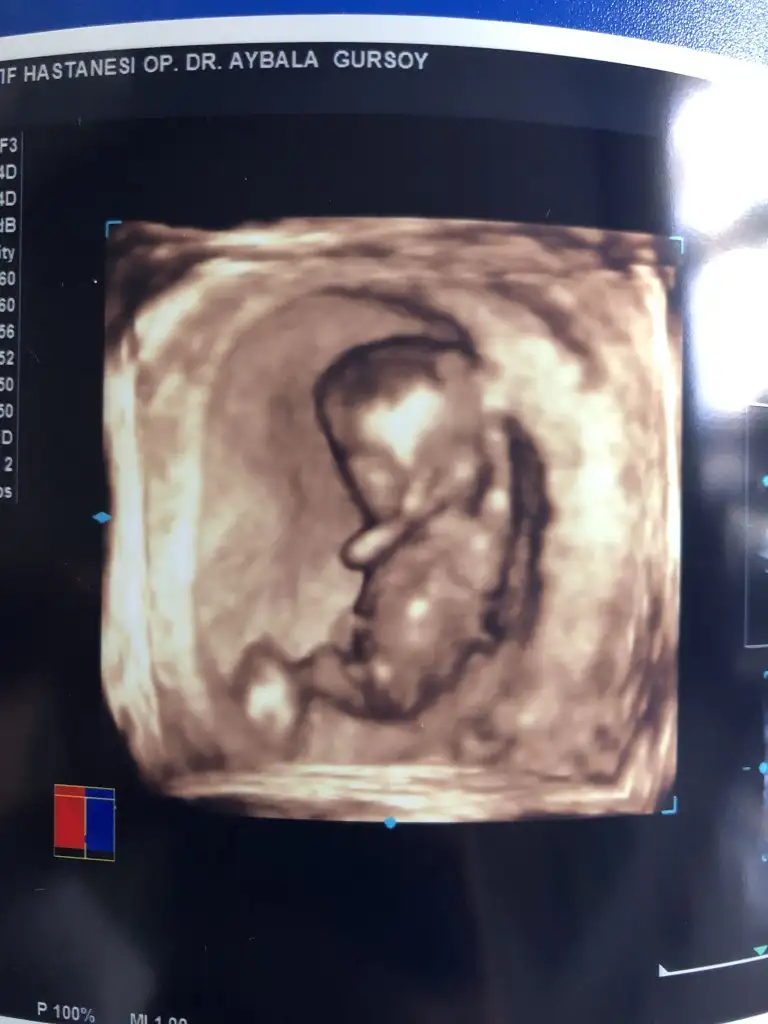

• IMG_20201211_205625.webp

IMG_20201211_205625.webp

20,7 KB · Görüntüleme: 38

Evet regl dönem bakınca 8 hafta doktor 9+3 dedi.